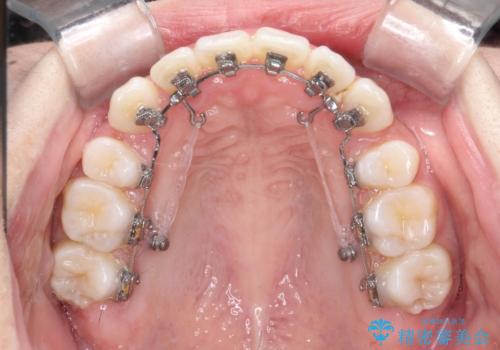

八重歯を改善!美しい口元を実現するハーフリンガル矯正

- 矯正装置

- ハーフリンガル

- 前歯のガタツキと口元のコンプレックスを解消するために来院されました。

ハーフリンガルワイヤー矯正で治療を開始しました。

ハーフリンガル矯正は、見た目を気にせずに矯正治療ができる方法です。この治療法は、八重歯や前歯のガタツキを効果的に改善します。特徴として、ワイヤーが上の歯の裏側に装着されるため、装置が外から見えません。これにより、治療中も自然な笑顔を保ちながら安心して治療を続けることができます。歯並びの悩みを持つ方にとって、非常に魅力的な選択肢です。